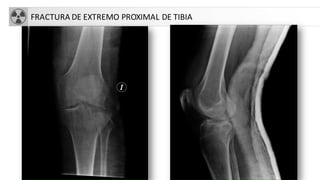

• Fx extremo proximal tibia

FRACTURA DE EXTREMO PROXIMAL DE TIBIA